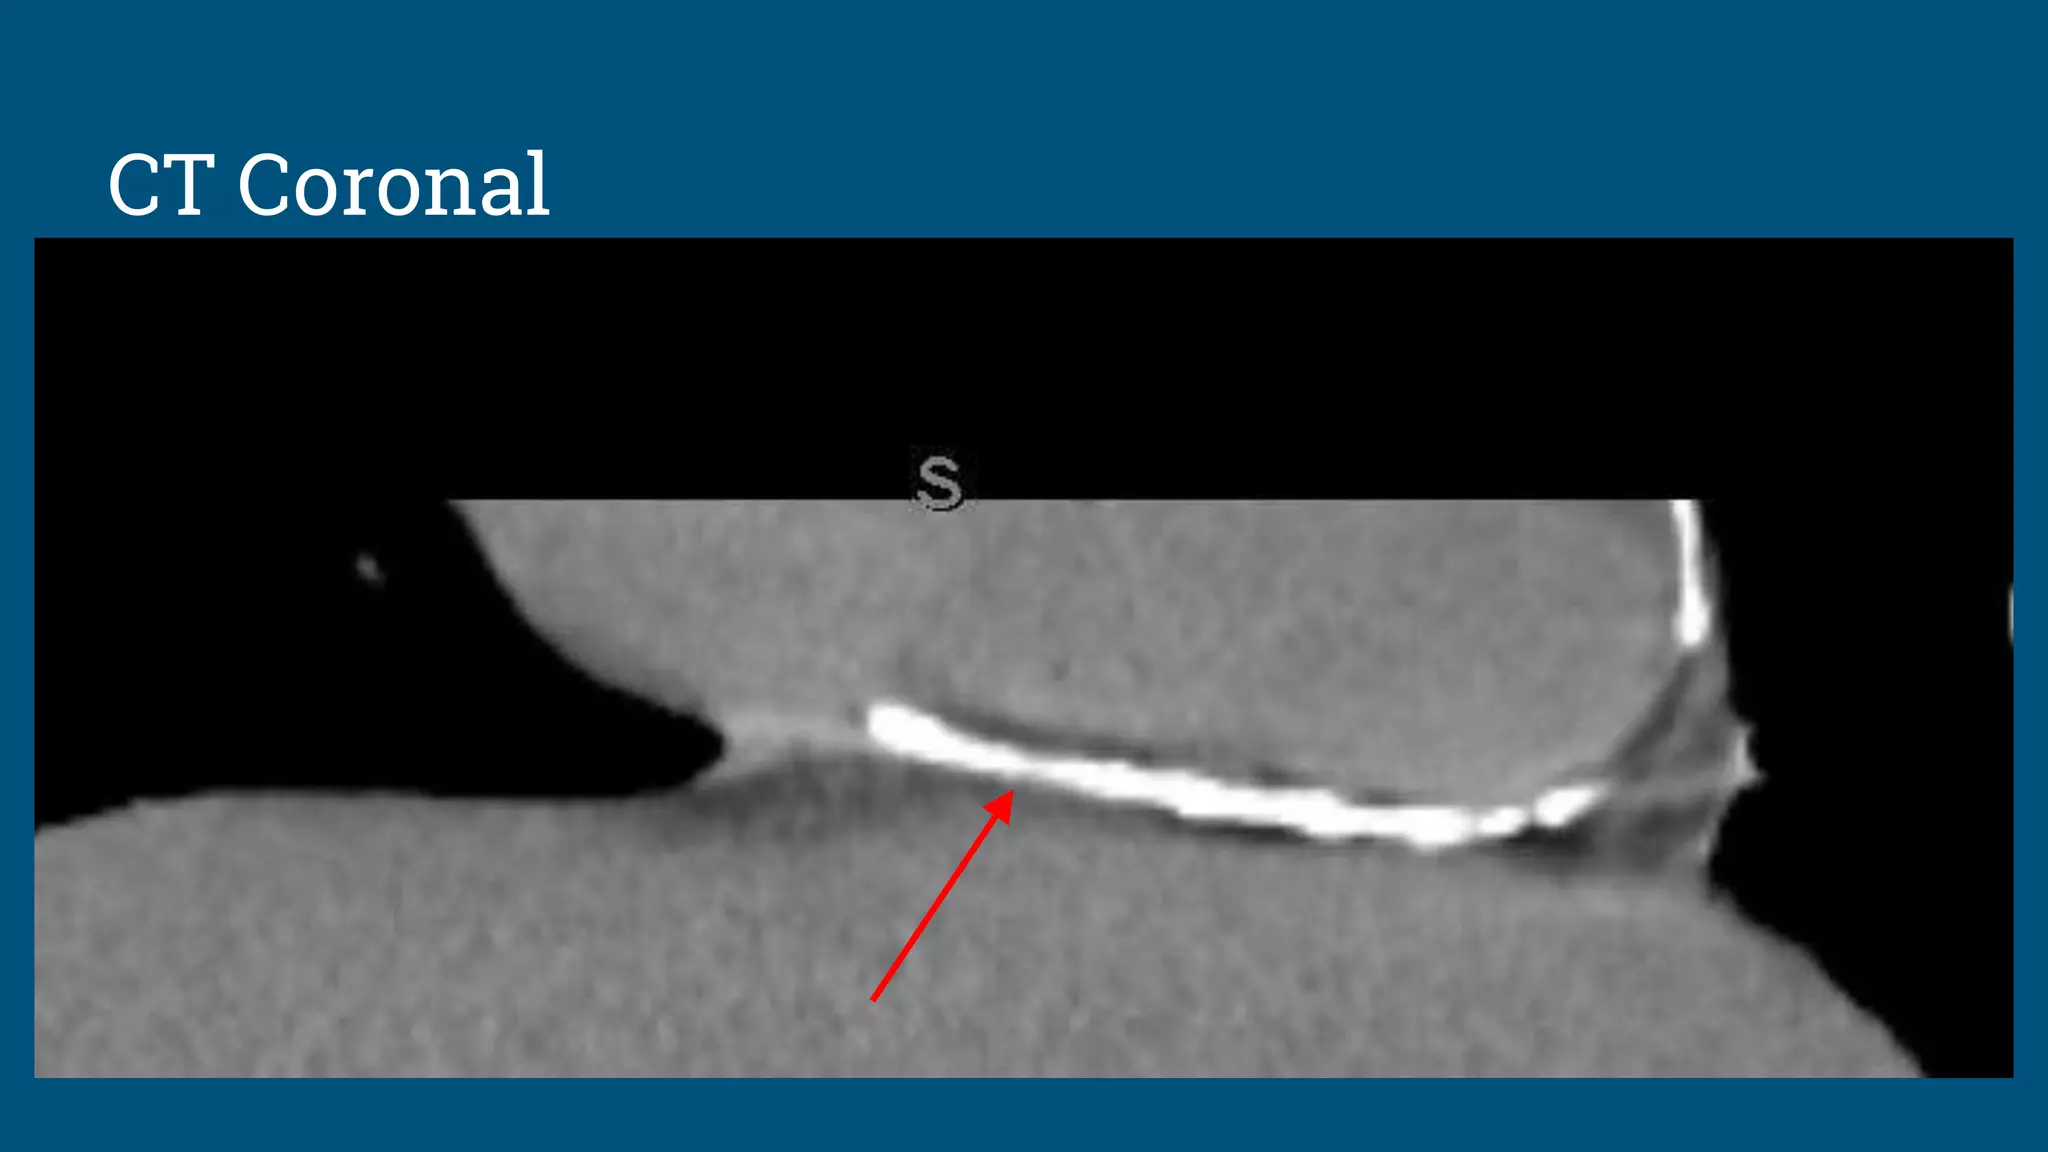

The patient is an 18-year-old male who presented with fever, abdominal pain, and dark urine 6 weeks ago and was diagnosed with mononucleosis. Further imaging found incidental pericardial calcifications. The patient has since developed dyspnea and palpitations. On exam, jugular vein distention and hepatosplenomegaly were present, as well as a precordial knock. Imaging and testing showed calcific constriction of the pericardium consistent with calcific pericarditis.